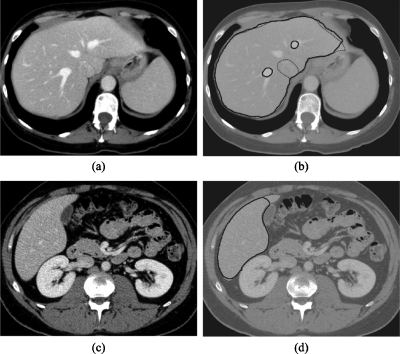

Figure 3 illustrates the intermediate images taken from each step of our scheme for an example case. The noise in the original CT image in Fig. 3a was reduced by the anisotropic diffusion filter, while maintaining the liver structures such as the portal vein and the liver border, as shown in Fig. 3b. A scale-specific gradient magnitude filter was applied to the noise-reduced image to enhance the liver boundary, as shown in Fig. 3c. The nonlinear grayscale converter enhanced the liver boundary for the use of the subsequent geodesic active contour segmentation, as shown in Fig. 3d. Finally, the liver was extracted by using the fast-marching and geodesic active contour level-set segmentation, as shown in Fig. 3e. After the extraction, the median filter was applied for removal of impulse noise in the extracted liver. Liver volumes were calculated using the extracted liver regions.

Figure 3.

Illustration of the resulting images at each step in our scheme. (a) Original CT image. (b) Anisotropic diffusion noise reduction. (c) Scale-specific gradient magnitude calculation. (d) Nonlinear grayscale conversion. (e) Geodesic active contour segmentation.